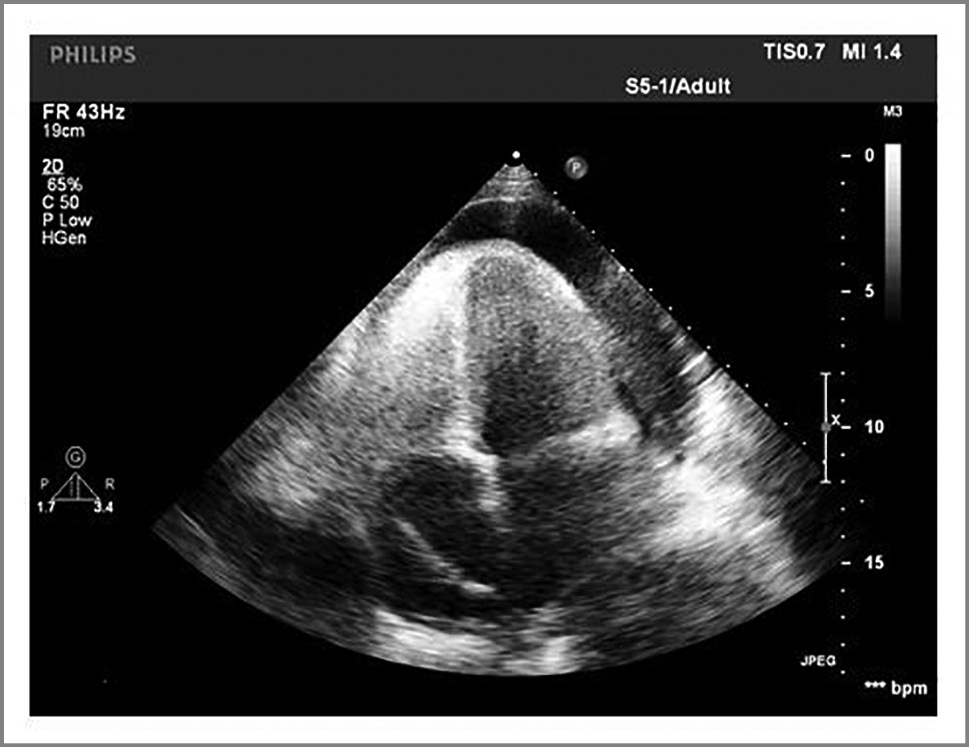

КТ органов ГК, 17сентября 2021 г. В полости перикарда определяется жидкость 30 мм (по задней стенке). Стенка перикарда не накапливает контрастное вещество. Восходящая аорта до 31 мм, нисходящая 22 мм. Легочный ствол 26 мм. Заключение: гидроперикард, двусторонний гидроторакс, в легких определяются небольшие участки фиброза (поствоспалительные изменения), пневматизация и васкуляризация легочной ткани не изменены, лимфатические узлы средостения не увеличены (рис. 4, a, b, c, d)

Рис. 4. Компьютерная томограмма сердца больной К.: a, b – аксиальная проекция; c – корональная проекция; d – сагиттальная проекция.

Fig. 4. Computer tomogram of patient K.’s heart: a, b – axial projection; c – coronal projection; d – sagittal projection.